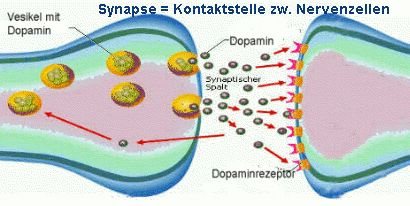

Damit diese, uns mental verändernden Botschaften von einer Nervenzelle zu ihren

Partnerzellen übertragen werden können, sind sie als Fährboote zwischen ihnen notwendig. Dabei sind sie unsere selbst produzierten Überträger- und Signalmoleküle, die alle biochemischen Botschaften zwischen ihnen übermitteln. Ohne sie ist keine Kommunikation im Gehirn möglich. Deshalb liegen sie jeder Emotion, jedem Gefühl, jeder Stimmung, allem

Denken, jedem Gedanken, allem Lernen, jeder Entscheidung, jeder Erinnerung, jeder Bewegung und allem was wir tun oder lassen zugrunde. Alles, was in unserem Gehirn abläuft

ist an sie gebunden.

Dopamin: Weit mehr als nur der Botenstoff der Lust und des Vergnügens

Der entscheidende Botenstoff zum Aufbau unserer Glücksempfindungen ist Dopamin in Verbindung mit Noradrenalin. Dabei wirkt Dopamin wie eine reizvolle Verführerin auf einer Südsee Insel, bei deren Anblick wir uns

sehr gut fühlen. Ihr Anblick löst in uns

Wollen, Begehren, freudige Erwartungen schöner Umstände in unserer Fantasie, Motivation, Antrieb, Aufmerksamkeit

und Interesse aus und hält sie aufrecht. Dabei wirkt Dopamin wie ein Scheinwerfer, der unsere Aufmerksamkeit auf alles denkbar Angenehme, Erfreuliche und Vergnügliche lenkt, bündelt und uns vorwärts, voran, hin zur Erreichung unserer Ziele treibt.

Dopamin, seine D1-, D2-, D3-, D4-, D5-Rezeptoren, beschwichtigend wirkenden D2-,

D3–Autorezeptoren, sein Wiederaufnahme-Transporter DAT und

Abbau-Enzyme COMT und MAO A spielen dabei eine ausschlaggebende Hauptrolle.

Andererseits ist das Gegenteil aber leider auch wahr: Ohne genug Dopamin

machen wir nichts, rein gar nichts, keinen Handschlag und keinen Finger krumm, weil zuwenig Dopamin in den Dopamin-Synapsen deckungsgleich mit Freud-, Antriebs-, Lust- und Interesselosigkeit

(psych.: Anhedonie) und chronisch mittel- und schwerdepressive Menschen einen zu geringen Dopaminspiegel in ihren Synapsen haben.

Dopamin ist der maßgebliche Botenstoff zur Beschaffung aller

Arten von Belohnungshappen. Ein erhöhter Dopaminspiegel in den Synapsen ist deshalb mit allem Angenehmen, Erfreulichen und Vergnüglichen und ein zu niedriger Dopaminspiegel

mit chronisch schlechter Stimmung, mittelschwerer und schwerer Depression

untrennbar eng miteinander verbunden. Die folgenden zwei Grafiken zeigen im Überblick neuro- und molekularbiologische Lebensprozesse im Dopaminsystem: